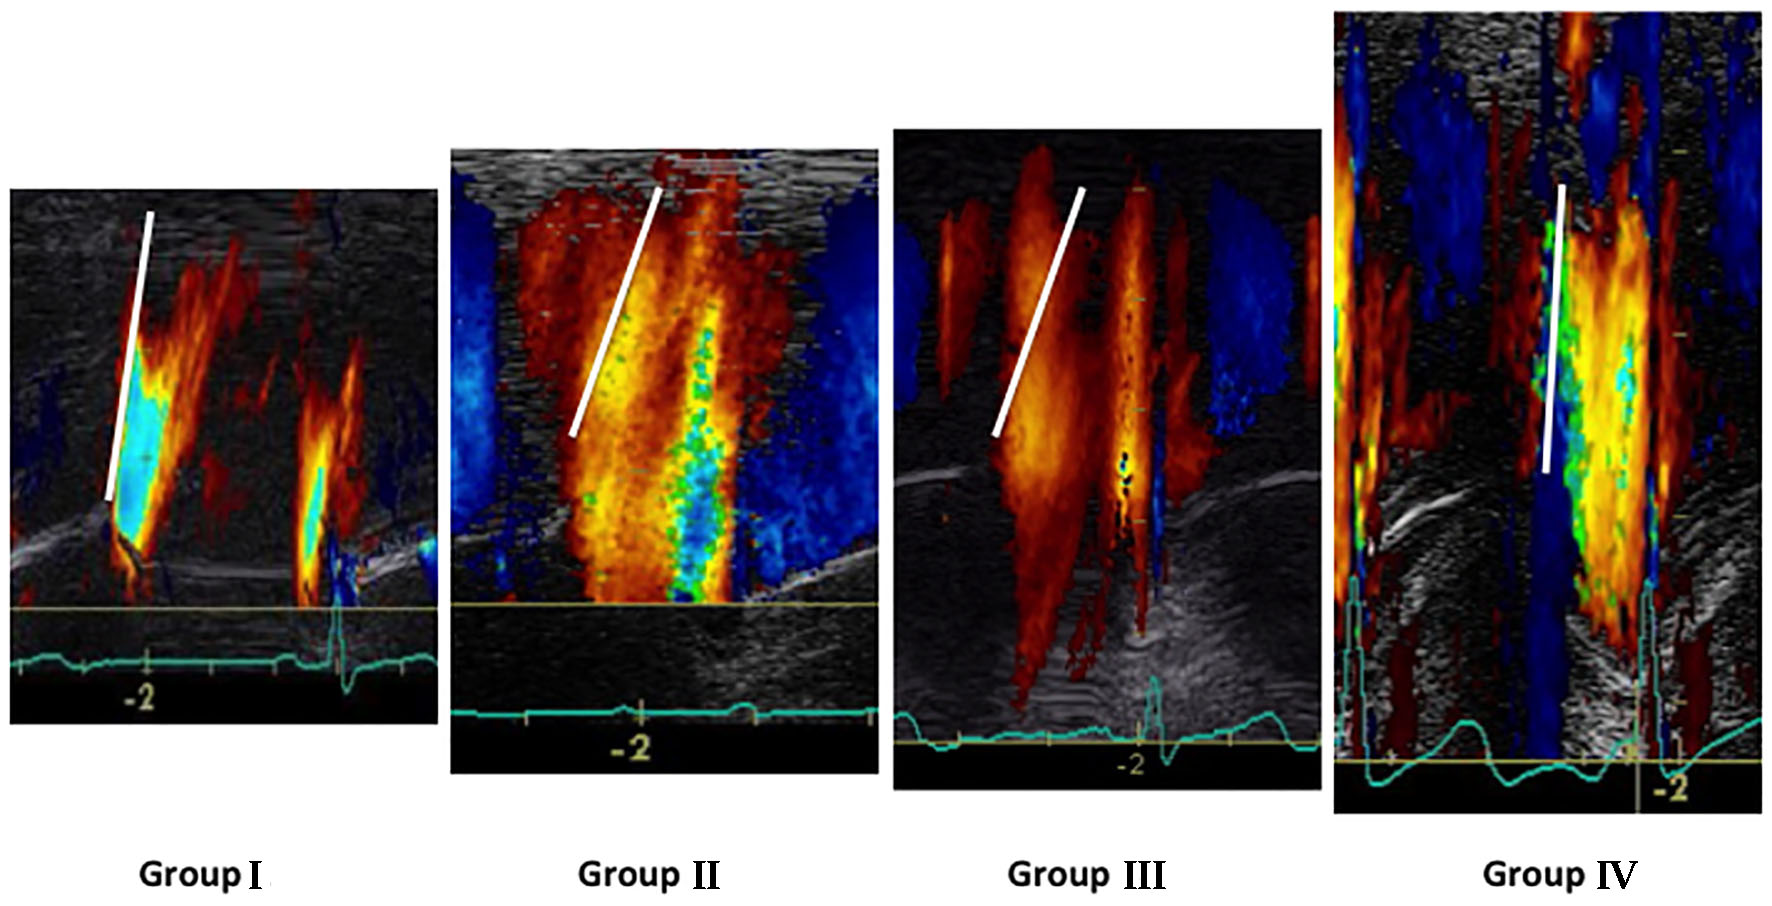

When we first examined Vp values (Fig. 2a), as expected, the lowest Vp values were noted in both LVDD patient groups (II and III) when compared to patients with normal LV diastolic function (P < 0.05). In contrast, the highest Vp values were recorded in PAH (group IV) patients when compared to the other three groups (P < 0.05). Additionally, in terms of PCWP, the highest values were found on group II: 15 ± 4 mm Hg and group III: 21 ± 5 mm Hg (P < 0.05) when compared to patients with normal LV diastolic function (group I: 12 ± 3 mm Hg) as well as PAH patients (group IV: 11 ± 3 mm Hg). As expected, the highest PCWP values were found in group III patients (P < 0.05) (Fig. 2b). Representative color M-mode Vp images for all four studied groups are shown on Figure 3.

![]() Click for large image | Figure 3. Representative color M-mode Vp images for the four studied groups. |